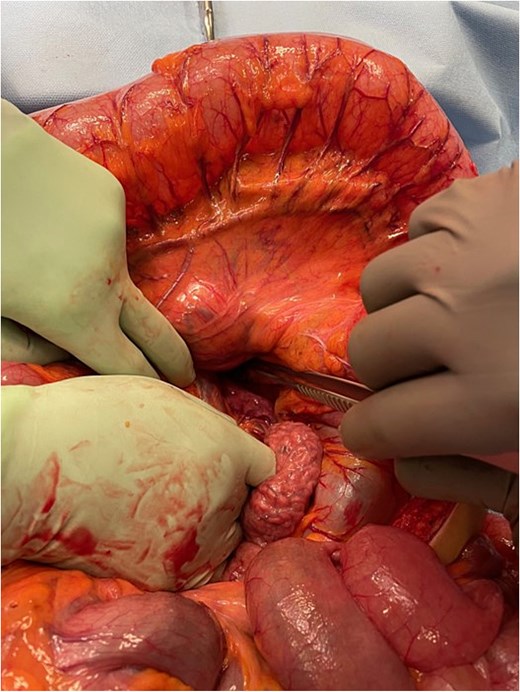

At laparotomy the proximal transverse colon and hepatic flexure were found herniating through the left paraduodenal recess into the lesser sac (Fig. 6). The herniating segment of large bowel was reduced. This segment was healthy and viable. A wide paraduodenal recess, narrow small bowel mesentery and mobile transverse colon exacerbated the herniation tendency into the lesser sac.

Intra-operative image demonstrating mesocolic defect through which the transverse colon had herniated.